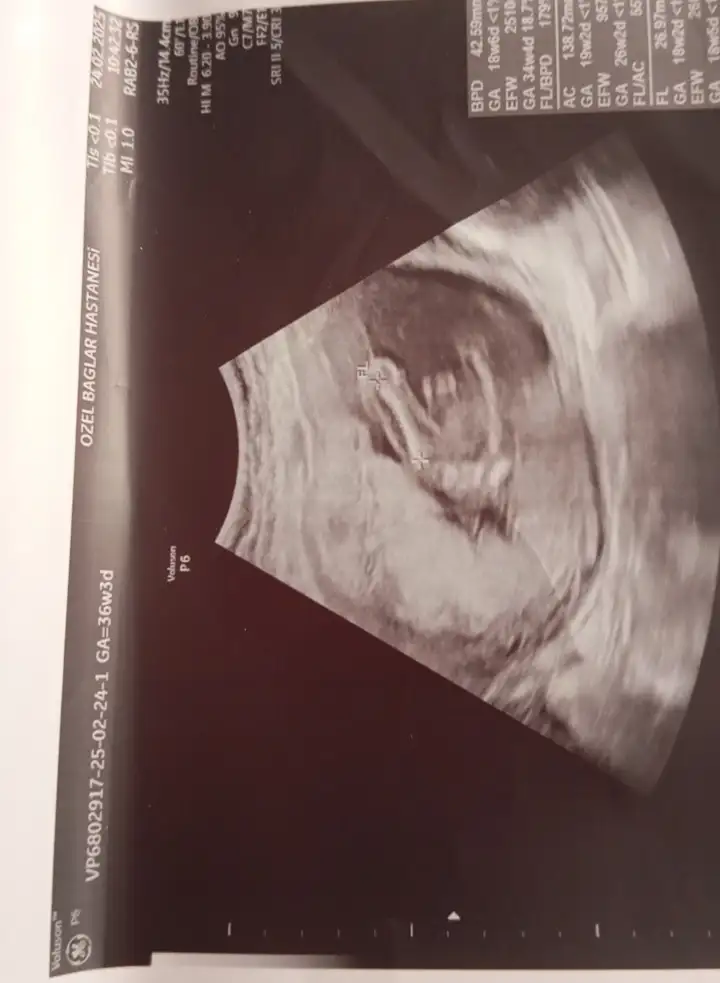

Sizce bu bebişin cinsiyeti nedirKuzum nub gözükmüyor tam o yüzden emin olmamakla birlikte benim kızıma benzettim kız diyim o yüzden

Hiç tahmin edemedim sallamiyimSizce bu bebişin cinsiyeti nedir

Erkek gibi geldi bana.2 li taramadan ultrason goruntum tahmin edebilecek olan var mi Eki Görüntüle 3575150